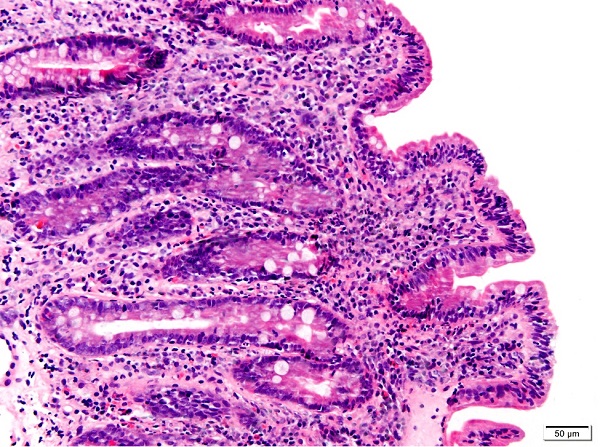

Se detecta la existencia de anticuerpos antitransglutaminasa diez veces por encima del límite alto de la normalidad (niveles de 629,00 IU, resultado positivo >10). Se completa estudio con endoscopia digestiva alta. La biopsia duodenal muestra atrofia vellositaria moderada con linfocitosis intraepitelial difusa e hiperplasia de criptas glandulares, sin evidencia de G. intestinalis, compatible con enfermedad celíaca 3b de Marsh modificado ( Fig. 3). Con el diagnóstico de enfermedad celíaca, se inicia dieta exenta de gluten y sulfato ferroso oral. De forma evolutiva, se constata la progresiva negativización de los anticuerpos, así como la desaparición del trastorno de la conducta alimentaria.